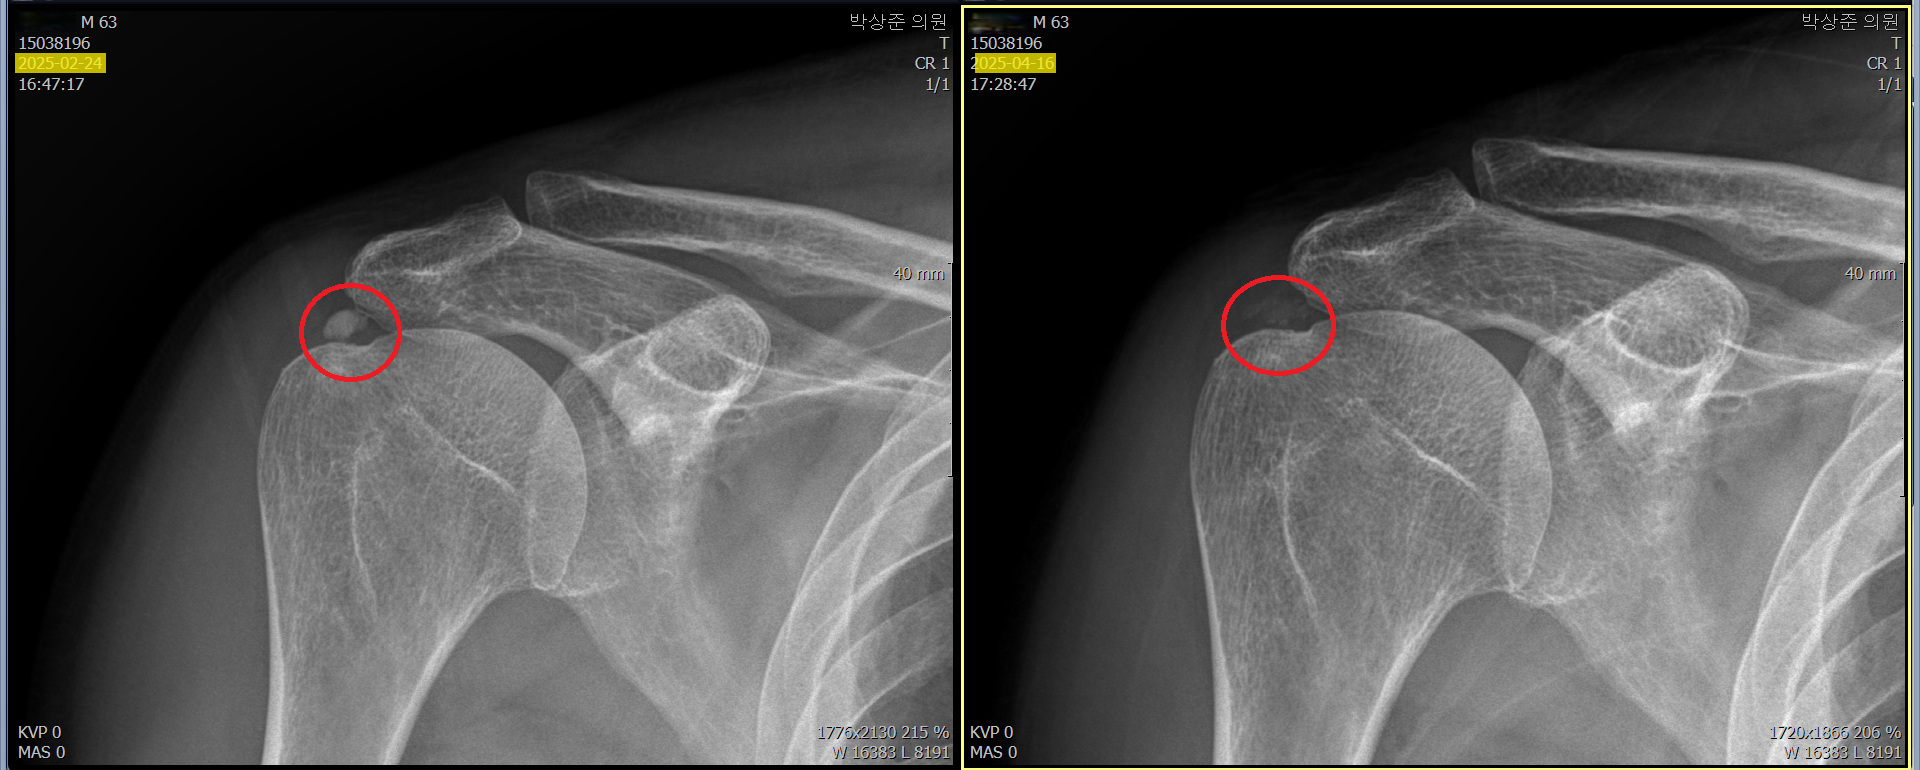

이렇게 5회 정도를 제거하고 찍은 비포 & 애프터 사진입니다. 최초의 빨간 동그라미 안의 석회가 거의 다 사라지고 약간 뿌연 정도로만 남아있는걸 확인할 수 있습니다. 이분은 이 치료 후 통증이 90% 가량 호전되었고 남은 통증은 시간이 지나면서 서서히 줄어들어서 지금은 통증이 거의 없는 상태로 지내고있습니다.